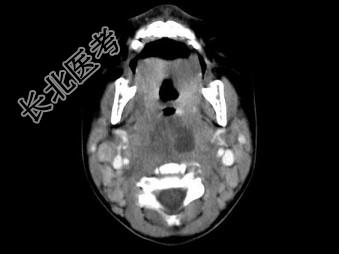

- 多项选择题10个月大的婴儿,发热, 曾患中耳炎,CT扫描如图所示, 正确的描述或诊断是 ( )

A、咽后壁软组织肿胀

B、其内密度不均

C、颈椎骨质未见明显异常

D、咽后壁脓肿

E、咽后壁寒性脓肿